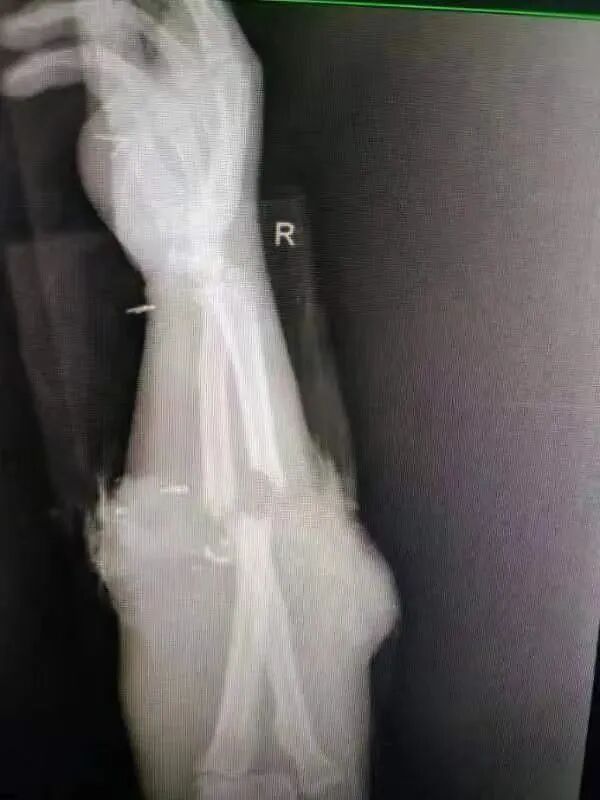

53岁的朱师傅(化名)是青山区武东地区某厂的工人。12日,他像平常一样在厂里干活,一不留神,整个右手不慎被传送带绞伤,巨大的碾压扭转力瞬间导致其右前壁几近离断,皮肤右上肢套状撕脱,大量铁屑沾染,导致严重畸形,失去正常外观,持续出血,现场惊心动魄、惨不忍睹。

右前臂毁损伤

尺桡骨双骨折

桡动脉断裂

桡神经、正中神经断裂、

前臂肌群损毁……

朱师傅病情危重,手术难度大,吴峰主任与华润武钢总医院医务科联系,启动联台手术机制。在武钢二医院团队第一轮积极清创进行的同时,武钢总医院骨科陈金武主任及关节手足外科王承良主任在了解朱师傅病情后立即赶赴武钢二医院。这是一例典型的严重肢体辗压离断伤,即使采取肢体再植的手术方式,肢体坏死率及残率仍然非常高。

因为大量铁屑沾染,手术清创异常困难,吴主任团队反复清理查找铁屑异物,并进行冲洗,待总医院专家到达,给予骨折临时固定,血管神经依次吻合,检查血管吻合后通畅,远端皮肤恢复红润。随后,将失活肌肉清创并减容后缝合,筋膜切开减压,创面封闭引流,屈腕位上肢外固定架固定,手术完毕,历时三个小时。